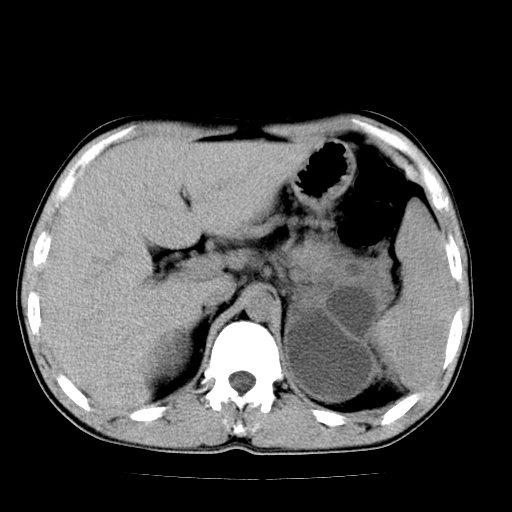

以下是引用天南地北在2007-4-30 13:36:00的发言:[br]支持慢性胰腺炎伴有假性囊肿

以下是引用andymaomao在2007-4-30 14:28:00的发言:[br]支持:1.慢性胰腺炎并假性囊肿形成可能;[br] 2.左肾形态稍增大,旋转不良。